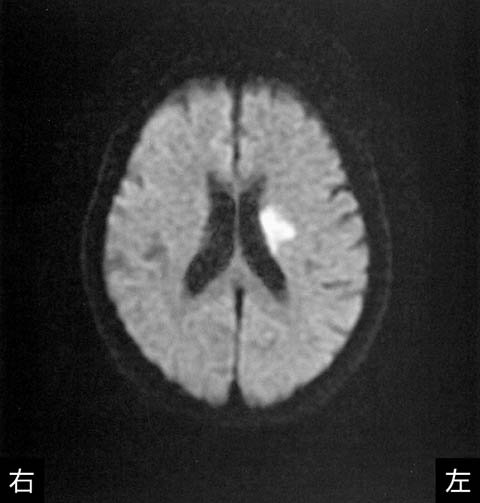

75歳の女性.右利き.脳梗塞を発症し救急車で搬入された.発症翌日に症状の悪化を認めた.発症3日目の頭部MRIの拡散強調像を下に示す.最も出現しやすい症状はどれか.

• 1.片麻痺

• 2.失語症

• 3.運動失調

• 4.嚥下障害

• 5.視野障害

解答: 1